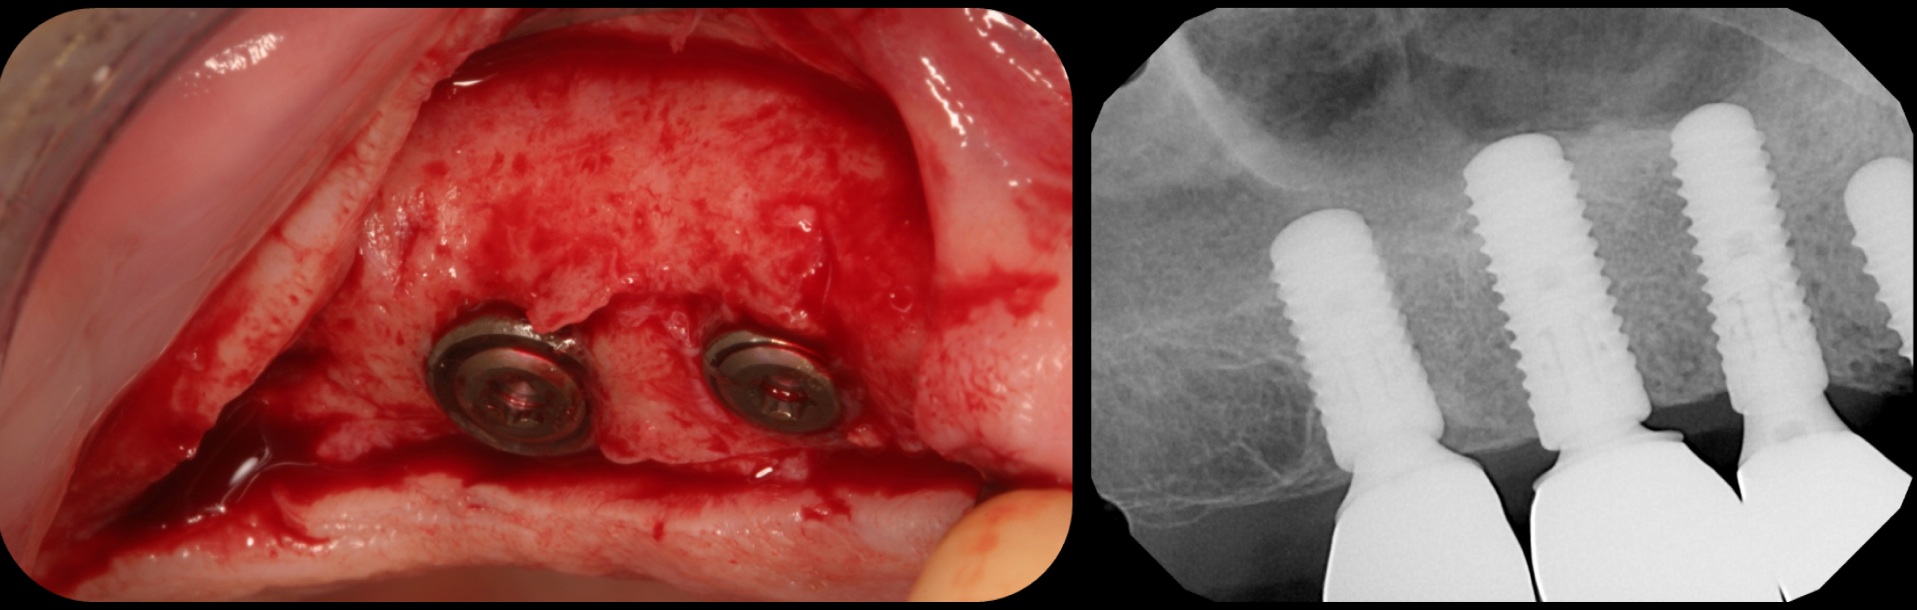

There is also “the Holy Grail” of regeneration, bone morphogenic protein (BMP), whose ability to stimulate the formation of bone where bone does not normally grow was discovered in the mid-60s by orthopedic surgeon Marshall R. Urist, who believed it was destined to bring osteogenesis under the control of surgeons; clinically, this recombinant DNA technology (recombinant human BMPs; rhBMPs) is being used in the regeneration of deficient sites planned for implant placement (Figure 11 through Figure 13).

Traditional sinus lift.

Fig. 11

Implants plus BMP without bone graft.

Fig. 12

Bone regeneration and implants loaded in 16 weeks.

Fig. 13